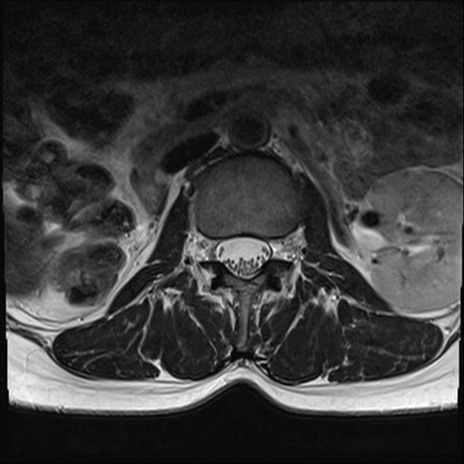

【整形】TIPS症例4 腰椎MRI T2WI(横断像)

腰椎MRI

横断像と矢状断像